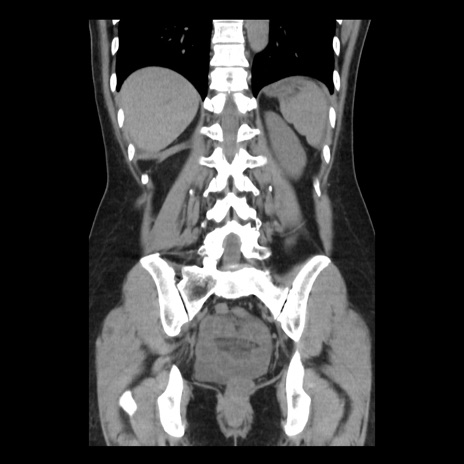

症例10(冠状断像)

【症例】 50歳代女性

【主訴】 腹痛

【現病歴】前日生レバーを食べた。今朝に排便あり。 昼前に突然発症の腹痛を生じ、当院救急外来を受診した。

【既往歴】 子宮筋腫にてで子宮全摘後

【身体所見】 意識清明、腹部:平坦、軟、下腹部やや左を中心に圧痛・反跳痛あり、筋性防御あり

【データ】WBC 7800、CRP 0.07